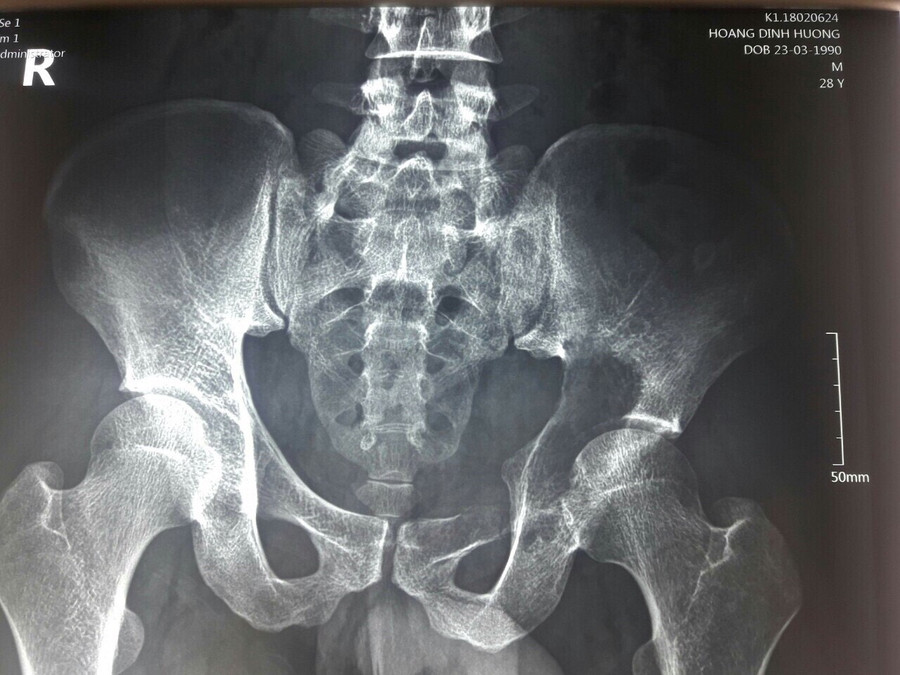

Sau khi thăm khám và làm các chỉ định cần thiết, các bác sĩ bệnh viện K nhận định có một khối u ở vùng ổ cối xương chậu phá huỷ gần hoàn toàn ổ cối và phát triển vào ổ bụng bệnh nhân tạo thành một khối đường kính khoảng 10cm.

Kết quả sinh thiết chẩn đoán xác định u tế bào khổng lồ. Chỉ định phẫu thuật được đặt ra với mong muốn lấy bỏ khối u triệt để và tạo hình lại khớp háng để giúp cho bệnh nhân sinh hoạt vận động trở lại.

Sự phá huỷ hoàn toàn vùng đáy ổ cối làm cho khớp háng mất chức năng gần hoàn toàn, bệnh nhân không có khả năng tỳ đè chịu lực trên chân tổn thương, còn các động tác vận động không chịu lực của khớp háng.

| Phim chụp sau phẫu thuật |